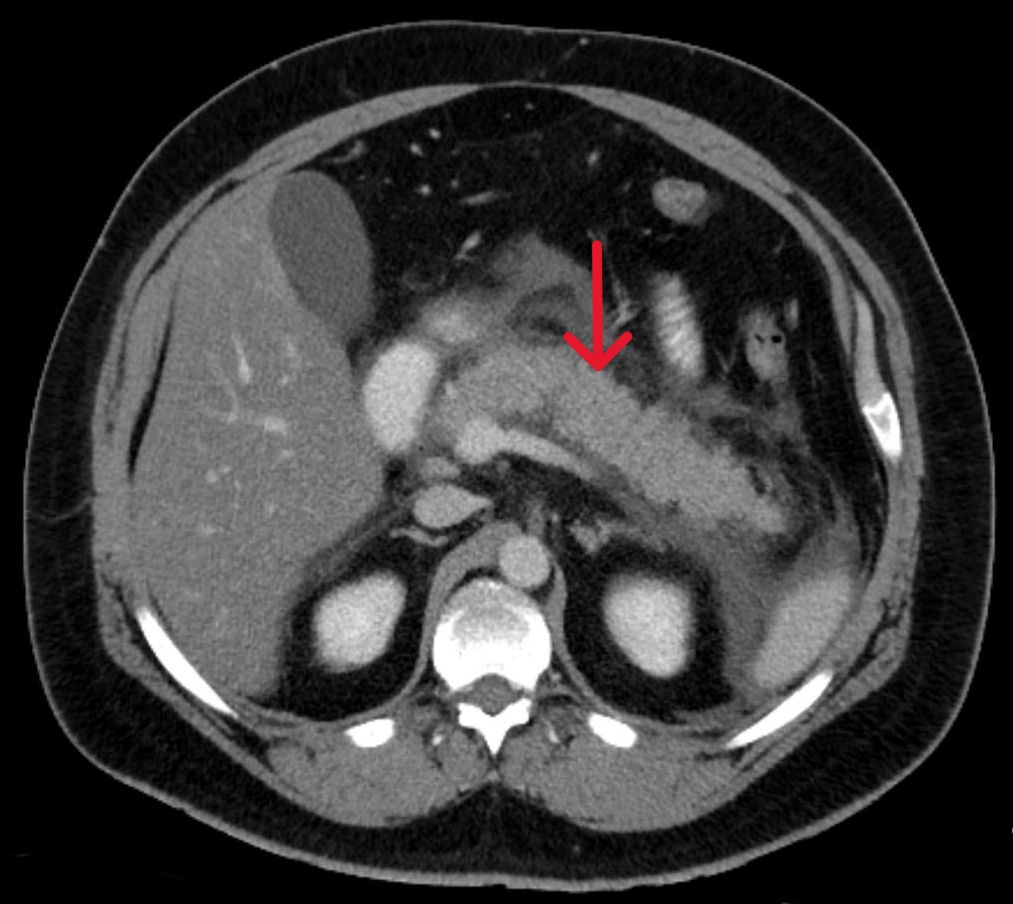

조영제를 사용한 CT 스캔은 일반적으로 통증이 시작된 지 48시간 이상 지난 후에 시행한다. 이는 췌장 조직의 괴사 여부와 췌장 주변의 액체 저류 상태를 평가하고 질병의 중증도를 예측하는 데 도움이 된다. CT 스캔을 너무 일찍 시행하면 실제보다 상태가 괜찮다고 잘못 판단할 위험이 있다.[33]

- '''복부 CT''': 일반적으로 췌장염 증상 발생 후 48시간 이상 지난 시점에서 조영제를 사용하여 CT 촬영을 시행한다. CT는 췌장 조직의 괴사 여부, 췌장 주변의 액체 고임 등을 평가하고 질병의 중증도를 판단하는 데 중요한 정보를 제공한다. 너무 이른 시기에 CT 검사를 시행하면 병의 상태를 정확히 반영하지 못하여 잘못된 판단을 내릴 수 있다.[33]